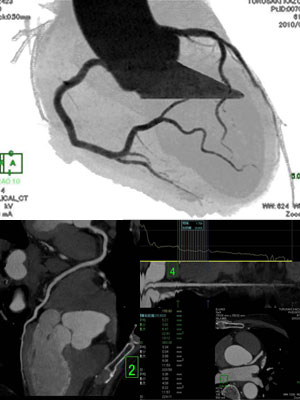

心臓CT検査

• 64列の高性能CT装置で委託検査を多数行っています

• 要予約にて、造影剤問診、同意書、内服状況を確認させて頂きます

• ご紹介時には、PDFの書面に記載頂き来院ください

心臓C